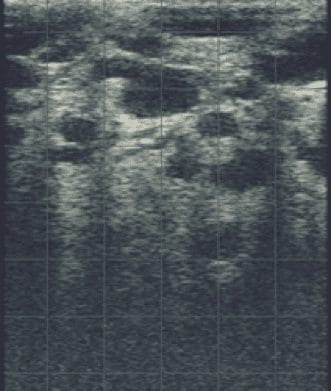

3 -Bovine udder with mastitis caused by Trueperella pyogenes.

Figure 3 is an ultrasound image of a bovine udder affected with mastitis caused by Trueperella pyogenes. This is characterized by the presence of multiple, hypoechoic regions throughout the parenchyma. Bacterial milk culture confirmed the causative agent.